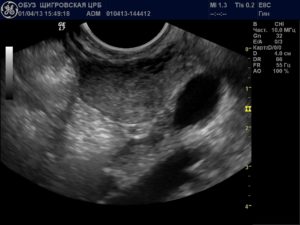

Многих женщин интересует, на какой день цикла делать УЗИ, чтобы максимально эффективно определить патологию. Конкретных рекомендаций по миоме нет, но в большинстве случаев УЗИ рекомендуется делать с 8 дня по 20 день цикла, когда гормональная система женского организма пребывает в состоянии относительной стабильности.

Чаще всего этот недуг проявляется спонтанно и протекает без особых симптомов. Наиболее эффективный метод ее выявления – ультразвуковое исследование. Для того чтобы диагностировать миому на ранней стадии достаточно проходить ультразвуковое исследование 1 раз в год. Суть метода заключается в том, что ультразвуковые волны отражаются от тканей.

Главной особенностью, которая позволяет отличить миому от беременности является фаза цикла, на которой проводится исследование.

Как правило, специалисты рекомендуют проводить исследования на 5 или 7 день после окончания месячных.

И все же ведущим диагностическим мероприятием, которое позволит определить наличие беременности либо миоматозных узлов в полости матки остается ультразвуковое исследование.

Благодаря активному развитию данной методике, выявление эмбриона в полости матки возможно уже на ранних сроках. При стандартном, абдоминальном УЗИ возможно установить беременность сроком от 4-5 недель.

Более современным и популярным способом трансвагинального УЗИ, возможно установить факт беременности, начиная со 2 недели после оплодотворения.